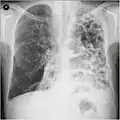

A chest X-ray is not useful to establish a diagnosis of COPD, but it is of use in either excluding other conditions or including comorbidities such as pulmonary fibrosis and bronchiectasis. Characteristic signs of COPD on X-ray include hyperinflation (shown by a flattened diaphragm and an increased retrosternal air space) and lung hyperlucency.[5] A saber-sheath trachea may also be shown that is indicative of COPD.[111]

A CT scan is not routinely used except for the exclusion of bronchiectasis.[5] Pulse oximetry measurement of peripheral oxygen saturation is recommended in people with clinical signs of respiratory failure or right heart failure.[5] An analysis of arterial blood is recommended in those with a peripheral oxygen saturation of 92% or less to determine actual blood oxygen level and assess for high levels of carbon dioxide in the blood, which may have therapeutic implications such as need for non-invasive ventilation or oxygen supplementation.[10] WHO recommends that all those diagnosed with COPD be screened for alpha-1 antitrypsin deficiency.[40]